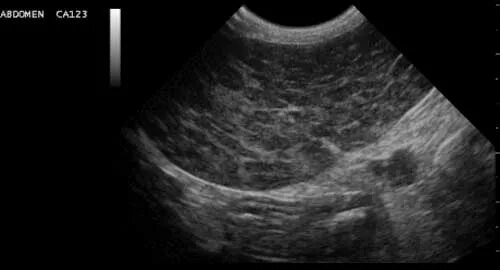

Диффузные изменения селезенки